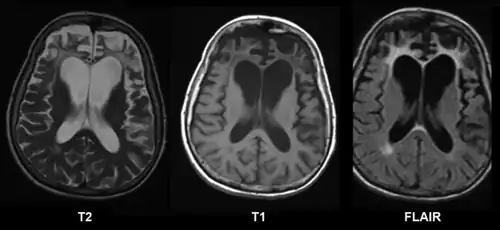

CT and MRI are most commonly used to observe the brain for cerebral atrophy. A CT scan takes cross sectional images of the brain using X-rays, while an MRI uses a magnetic field. With both measures, multiple images can be compared to see if there is a loss in brain volume over time.[20]

Difference from hydrocephalus

Cerebral atrophy can be hard to distinguish from hydrocephalus because both cerebral atrophy and hydrocephalus involve an increase in cerebrospinal fluid (CSF) volume. In cerebral atrophy, this increase in CSF volume comes as a result of the decrease in cortical volume. In hydrocephalus, the increase in volume happens due to the CSF itself.[20]